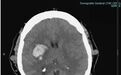

患者信息:45 岁女性,因「意识丧失,口角歪斜」入院。既往有高血压病史。

头部 CT 平扫显示右侧基底节区脑实质内出血,大小为 4.2x2.6cm,压迫右侧侧脑室。头皮不规则,可见多发类圆形和管状病变。